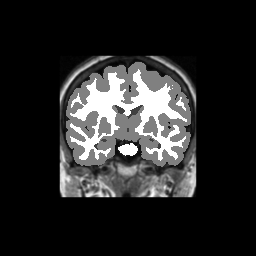

Accuracy is reported as Dice overlaps between a tool's segmentation and the Internet Brain Segmentation Repository (IBSR) manual segmentation for each of the 18 IBSR subjects. The inter-tool comparison (on the left below) shows the median Dice coefficient for each tissue class. The overlaps for FSL (from which the median values are drawn) are shown in the plot on the right.

Subject Accuracy (IBSR)

Overlap coefficients for each tissue class are shown here for each IBSR subject. Select a subject below to see the FSL results compared to other tools.